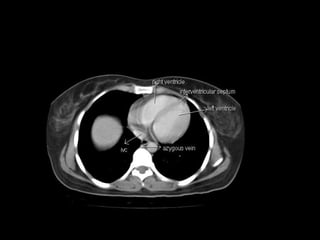

Radiographers use medical imaging equipment like X-rays and MRIs to produce images of patients' internal structures and organs. They are responsible for positioning patients, operating scanning machines, and ensuring quality images. Radiographers must have strong attention to detail, excellent communication skills, and the ability to work well under pressure to accurately capture anatomical features and diagnose any abnormalities.